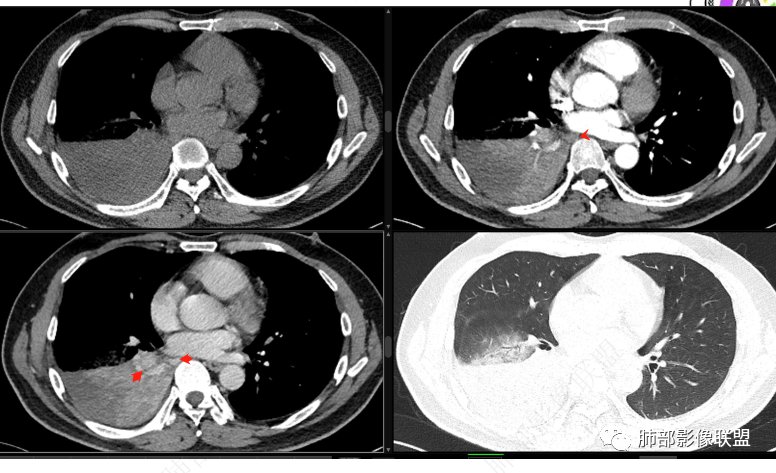

右肺下叶实变影,局部膨隆,边缘磨玻璃密度影,肺门区域明显强化考虑恶性,腺癌可能。

右肺下叶实变表现,强化和形态不考虑门口堵所致不张,枯树枝不明显,整个肺叶考虑肿瘤浸润,首先要考虑腺癌

右肺下叶实变,周围磨玻璃,近端支气管扩张,管壁凹凸不平,远端阻塞,可见粘液栓,不均匀强化,有低密度无强化影,其内血管显示尚可,考虑粘液腺癌,鉴别淋巴瘤

右下叶支气管结节,明显强化,远离支气管内粘液栓及肺不张,考虑肿瘤——类癌?涎腺肿瘤?鳞癌?强化明显,类癌可能性更大一些。

右肺下叶阻塞性肺不张,粘液栓,边缘磨玻璃影,良性,谈栓,异物,恶,鳞,腺癌,类癌,男性,46岁,病程不长,似乎有强化,选类癌。

右下叶肿块外向内生长,支气管阻塞伴阻塞性炎症,不均匀强化,血管边缘模糊,考虑腺癌,鉴别类癌。

右肺下叶大片实变,密度不均匀,可见支气管充气征及粘液区,右肺下叶支气管内结节影,下叶支气管阻塞,病灶前下可见磨玻璃影,右侧积液,考虑粘液腺癌,鉴别类癌?

腔内占位。远端阻塞,男性,考虑恶性可能性大,鳞癌先

支气管腔内结节,明显强化,远端阻塞性病变,中年男性,考虑类癌,鉴别鳞癌。

右下叶支气管狹窄,内见高密度强化结节,远端大片不张实变,实变内可见多发粘液拴,整体观察实变似有见缝就针的感觉,综和分析考虑粘液表皮样癌,其次考虑类癌

中央型肿瘤pk周围型肿瘤  。壮年男性,热咳一周伴气喘,中性白细胞升高,临床是个感染过程。支持中央型病变的证据:1  肺门明显强化结节 2 横s征  3 支气管粘液栓  4 主支气管变窄,似见冰山征      支持周围型病变:1 按叶段塑形  2 血管造影征  3 病灶内弥漫高强化  4 周围伴磨玻璃灶,但境界不清继发感染?误吸?综合 中央型肿瘤可能大:类癌》鳞癌

右肺下叶不张,右下肺门区高强化结节,似乎呈冰山征,首先考虑类癌可能

右下肺门似见一结节影,明显强化,远端支气管黏液栓,右肺下叶不张,考虑类癌,次之黏液表皮样癌 腺样囊腺癌

右肺下叶支气管见结节灶继发右肺下叶膨胀不全,右肺中央局部炎性改变,下叶支气管结节动脉期明星强化,静脉期强化减低,首先考虑肺鳞癌,鉴别类癌、粘液表皮样癌。

首先血管未见明显侵犯、移位,提示病灶:炎性;肿瘤:外朝内——含粘液类腺癌(肺门淋巴结转移),腔内肿瘤(鳞癌、腺癌、类癌、小细胞、粘液表皮等)

从强化看:外周密度低,强化弱

就不太符合腔内肿瘤远端不张的表现,因为外围不张——强化明显

这一例反了

按这个特点周围要考虑肿瘤组织

腔内肿瘤,远端堵塞